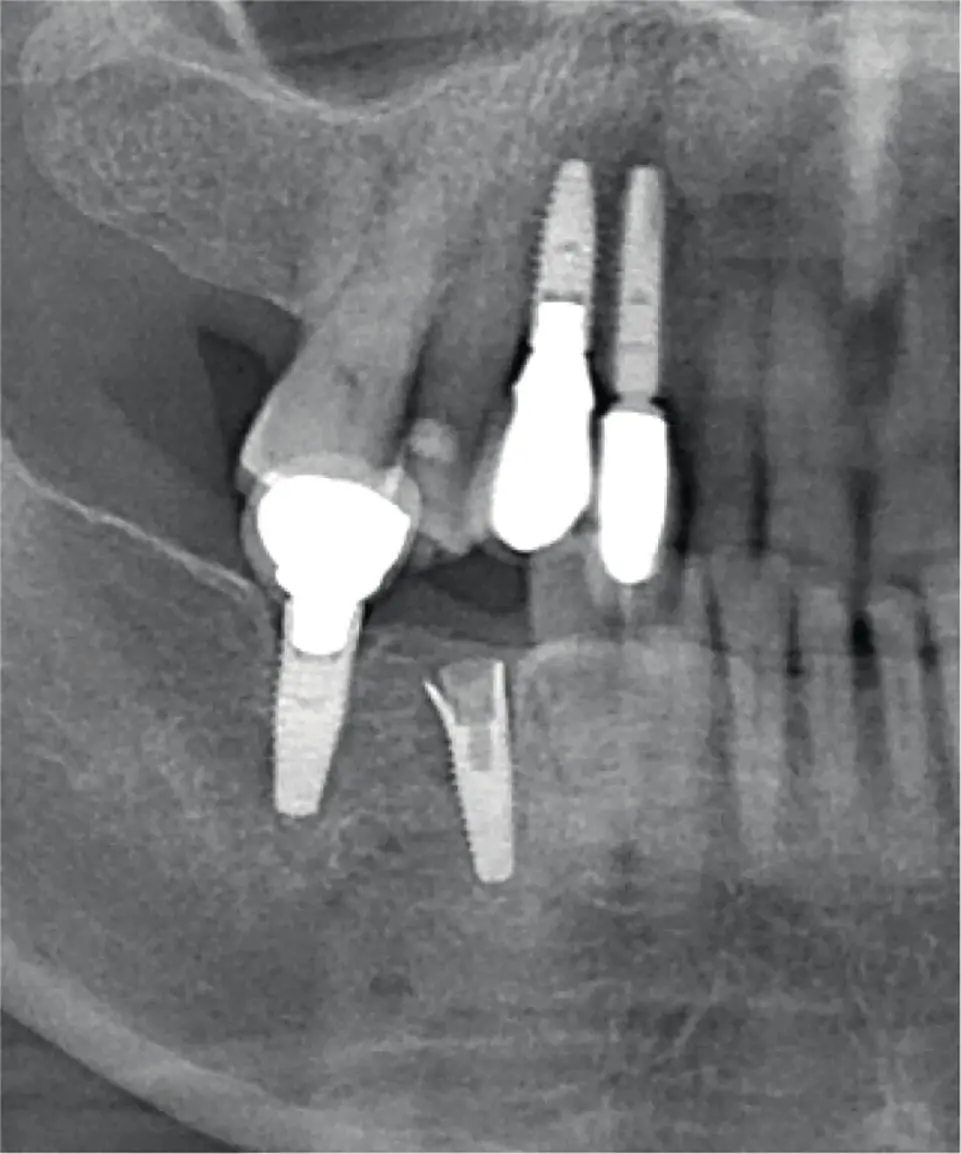

Fracture of the actual surgical implant fixture itself usually necessitates removal since the implant becomes nonrestorable ( Figures 3.20and 3.21). In most instances, the fracture can once again be related to excessive masticatory forces and occlusal loads, parafunctional habits, or poor occlusal schemes. These should be addressed and plans made to avoid similar circumstances that will almost certainly lead to the same poor outcome. Depending on the location of fracture, and whether or not the internal channel of the implant is intact, there are several methods by which a fractured implant can be removed. Initial attempts should be made at “simply” reversing the implant out of the bone. This may not be simple or straightforward, but maintaining the alveolar bone can be of great benefit when considering possible repeat implant placement. Under ideal circumstances, this implant can be replaced immediately at the time of removal of the fractured implant. A reverse torque wrench may be used, but if the implant internal channel has become compromised, a reverse torque wrench may not seat appropriately for use. In these cases, the implant will require removal with a surgical trephine bur [42]. The narrowest possible trephine that will fit around the implant should be selected in order to maintain as much native bone as possible. These burs are generally run at slower speeds and should be used in unison with hand instrumentation in order to mobilize the fractured implant, similar to an ankylosed tooth. Once removed, the fractured implant should be inspected to confirm complete removal and the surgical site reconstructed in a suitable manner, possibly with bone grafting or GBR. A replacement implant of a wider diameter may be considered for immediate replacement. The removal of multiple implants can create a large bony defect that may compromise the integrity of the jaw. In these instances, the surgeon and patient must have a preoperative discussion involving the possible need for additional fixation in order to treat and/or prevent possible mandible fracture. On rare occasions, the implant fracture may occur at such a level or in such a manner that the implant may remain restorable. Although this is far from ideal, the implant surgeon, restorative dentist, and patient must have a frank discussion about the option of retaining the compromised fixture versus removal and replacement. In the frail patient with minimal bone stock, it may be preferable to retain a restorable fractured implant and closely monitor to ensure no development of infection or component failure. In conclusion, no two clinical situations are exactly the same, and all factors must be considered when determining a final treatment plan ( Algorithm 3.8).

Fig. 3.20. Radiograph of fracture of the actual implant fixture.